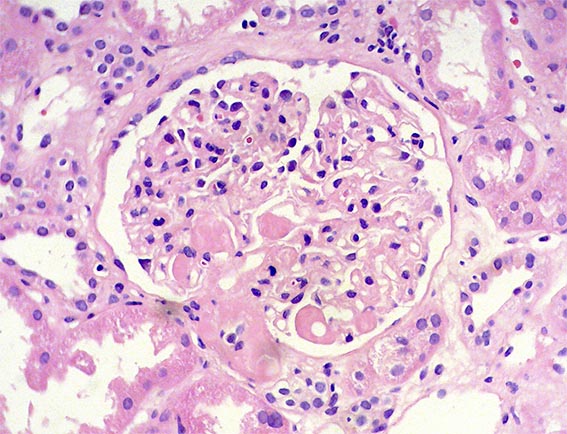

The patient is a 49-year-old man who was kidney transplanted nine years ago. Normal graft function, without proteinuria, until the 8th year, when he started to present mild proteinuria that gradually increased to 2.8 g/24 hours. Serum creatinine has also increased to 1.6 mg/dL.

Other tests: Hb: 9.5 mg/dL, Hto: 30.2 % (he has had multiple transfusions for anemia, since before transplantation), severe dyslipidemia: Triglycerides: 488, total cholesterol 480 mg/dL, VLDL: 209 mg/dL, LDL: 2 mg/dL, HDL: 3 mg/dL. Tests for autoimmunity, complement and viruses: Negative or normal. Ultrasound of the graft: Normal. On examination: Corneas opaque bluish with peripheral white halo, without visual impairment. No other alterations.

See the images of the biopsy.

Figure 2. H&E, X400.